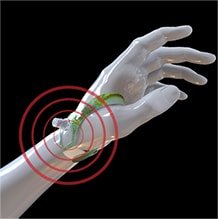

DISTAL RADIAL ACCESS

Distal radial artery access offers both patient and operator advantages. To help bring these benefits to your practice, we provide advanced training on the distal technique as well as innovative products to support your procedures, such as the first-to-market PreludeSYNC DISTAL™ Radial Compression Device.